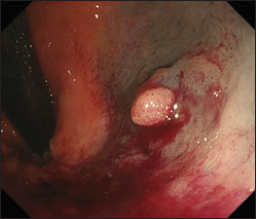

Figure 1:Total colonoscopy showed a polyp which was 5mm in size on the rectum below the peritoneal reflection; 39cm from the anus. Purpura was caused by the aspiration for endoscopic mucosal resection.

He was treated with medicines for high blood pressure hypertension, hyperuricemia, iron

deficiency anemia, and insomnia. A cecal cancer was diagnosed in him by Total Colonoscopy

(TCS) which was performed to check cause of fecal occult blood. We assessed that operation

was necessary to cure the lesion. In addition, there was a semi-pedunculated polyp which was 5mm size on the rectum below the peritoneal Reflection (Rb)

and we tried to perform Endoscopic Mucosal Resection (EMR) for

it immediately. However, we interrupted to perform EMR for it

because severe purpura was caused by the aspiration for injection

to submucosa (Figure 1). We confirmed spontaneous cessation of